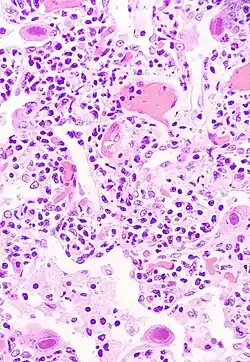

Pneumocytes infectés par le cytomégalovirus | ||||||||

Cytomégalovirus, journal d’hospitalisation est une œuvre d’Hervé Guibert publiée à titre posthume en 1992 aux Éditions du Seuil. Du au , l’auteur, atteint du sida, est hospitalisé. Il risque de perdre la vue à la suite d'une infection au cytomégalovirus. Il rédige ce journal quelques mois avant de mourir, le .